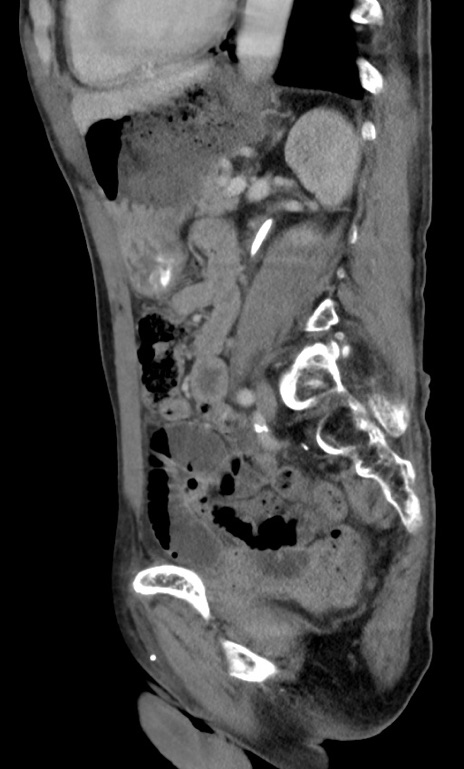

症例3(矢状断像)

【症例】 70歳代男性

【主訴】右鼠径部腫瘤、疼痛

【現病歴】本日朝より上記主訴あり、受診。

【既往歴】膀胱癌にて膀胱全摘、両側尿管皮膚瘻

【データ】WBC 5600、CRP 0.56